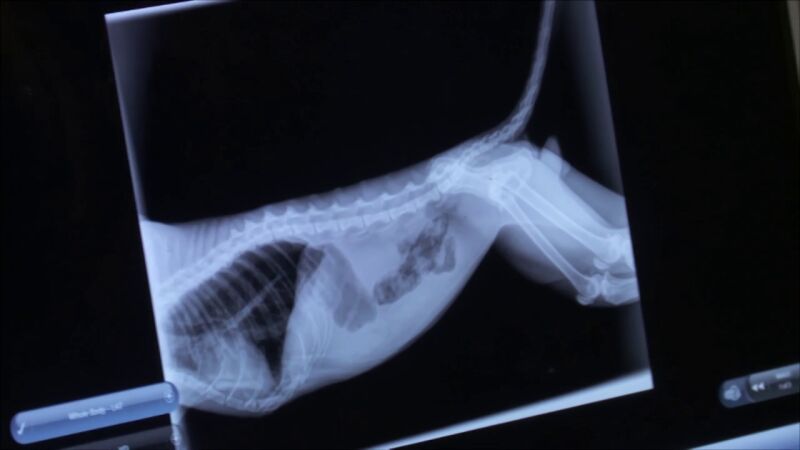

La doctora Emily se ha sorprendido al ver los resultados de la radiografía.

La doctora Emily ha decidido hacerle una radiografía para ver si alguno de sus órganos está dañado y si tuviese alguna fractura en una de sus patas, pero lo que ha visto le ha dejado anonadada.